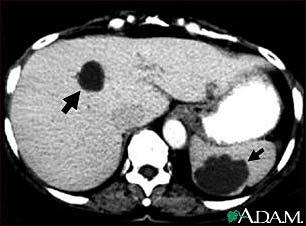

Liver and spleen cysts - CT scan

This abdominal CT scan shows multiple cysts in the liver and spleen. Note the dark circular cyst in the liver (left side of screen) and the large, irregular, circular cyst in the spleen (bottom, right side of screen).